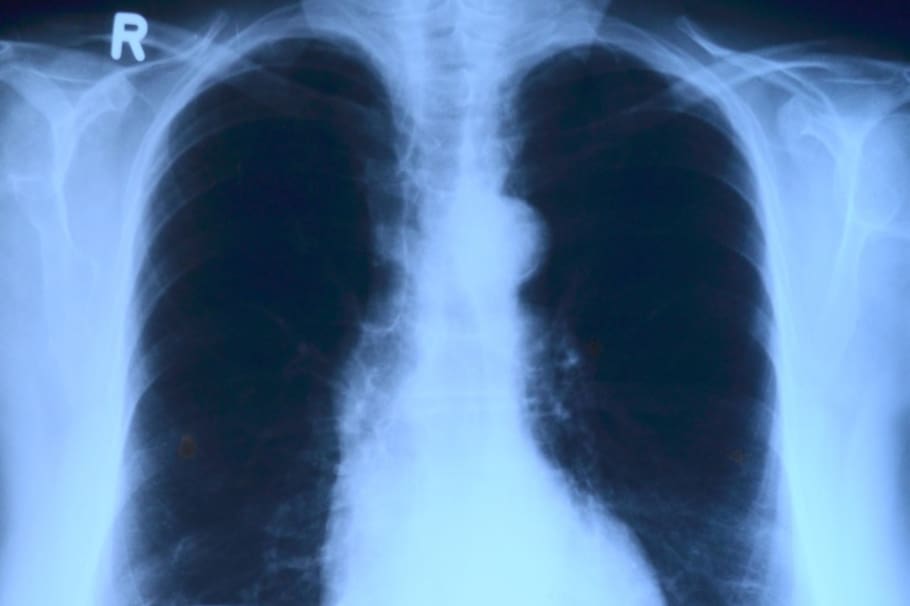

El liquido que se dirige a los pulmones durante un enema pulmonar puede acumularse en los alvéolos, que son las pequeñas bolsas de aire en los pulmones donde ocurre el intercambio de oxígeno y dióxido de carbono. Como resultado, las personas con edema pulmonar pueden experimentar dificultad respiratoria grave, lo que requiere atención médica inmediata.

El edema pulmonar se clasifica en dos tipos principales según su causa: cardiogénico y no cardiogénico.